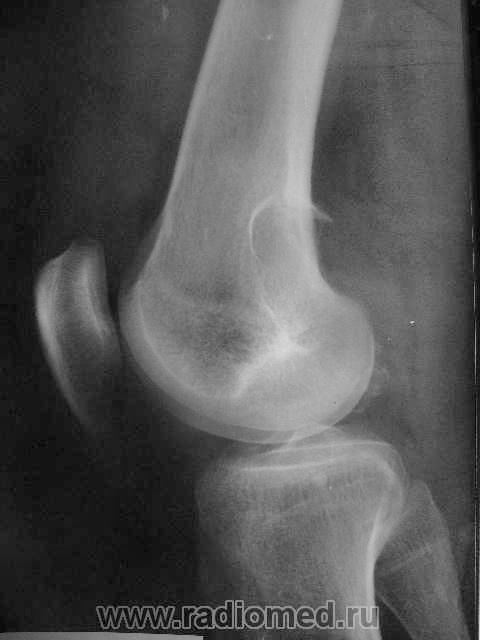

Здравствуйте, уважаемые коллеги! Сегодня в травмпункте принесли на описание снимки молодого человека 1984г.р. Травма, подвернул ногу. Жалобы характерные. Не наблюдался, не лечился. Прошу высказать мнение о характере патологии в метафизе бедренной кости.

Я склоняюсь к ГКО с кортикальным расположением, прорывом содержимого в мягкие ткани. А что думаете Вы? Т.к. снимок из травмпункта, поговорить с больным проблематично (я там совмещаю по вечерам).

На гигантоклеточную опухоль похоже, но не очень

Метафизарный кортикальный очаг фиброзной дисплазии. ИМХО.

какой красивый "козырек" по задней поверхности...

Расположение крупного очага деструкции эксцентрично (кзади) и вкрапления извести говорит в пользу солитарной хондромы, а местами нечеткие контуры ("скорлупа" теряется), "козырек" и  мягкоттканный компонент нацеливают на озлокачествление. Кроме того очень смущает структура прокс. эпиметафиза б/берц. кости. В любом случае, вижу прямые показания к активным действиям, начиная с биопсии.

И я за хондрому.

Спасибо за высказанные мнения. Интенсивная тень в проекции метафиза это артефакт на пленке. Больного я отправил на консультацию в специализированное учреждение, так что потеряться он не должен. Если узнаю результаты, то сообщу.